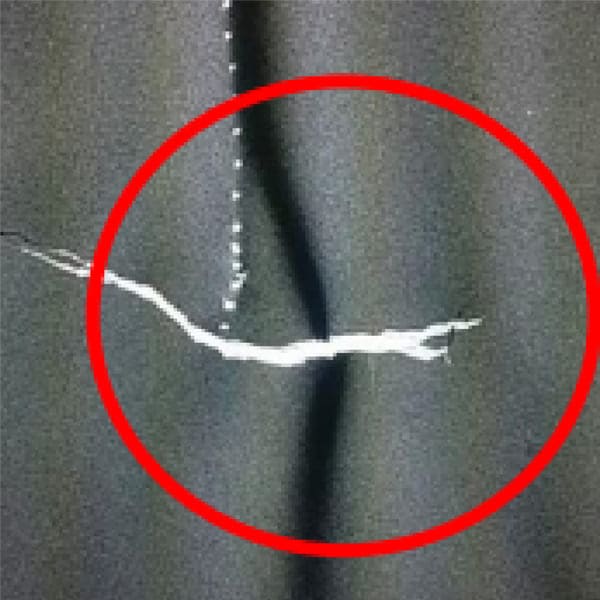

1. Déchirures

Les déchirures dans les tabliers plombés, en particulier celles de plus de 5,4 cm, nécessitent un rejet immédiat. Même les petites perforations autour des bords peuvent entraîner un échec, selon leur gravité. Utilisez l’imagerie par rayons X pour détecter les déchirures invisibles à l’œil nu.

Fissures

Les fissures dans le matériau protecteur plombé se forment souvent en raison d’un mauvais stockage ou de flexions répétées. Ces fissures compromettent la capacité du tablier à bloquer les radiations, rendant une inspection régulière indispensable.